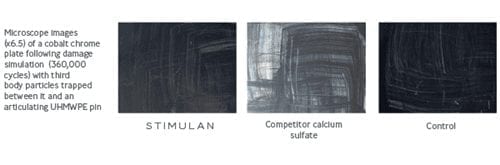

No third body damage13

Less scratching than competitor calcium sulfate and PMMA.